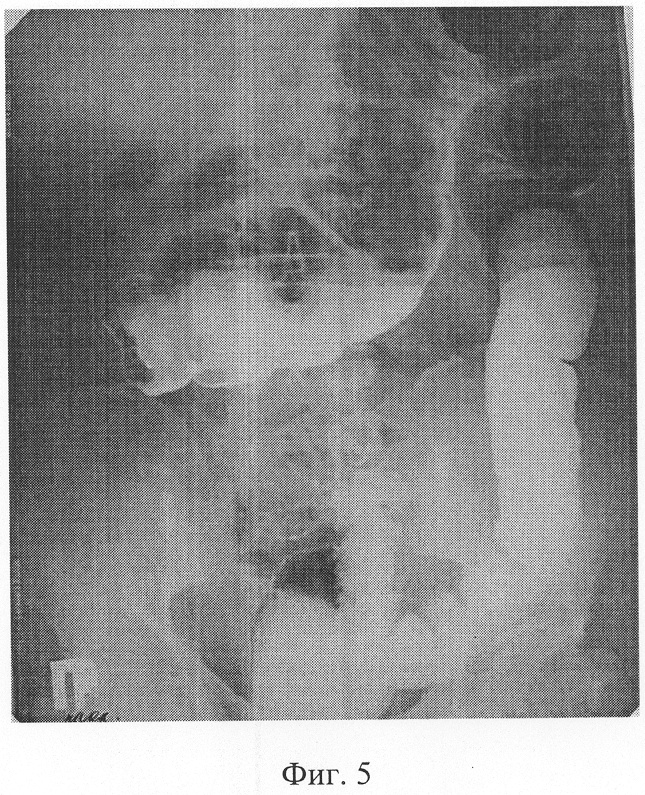

фиг.5 – ирригограмма больной П. после операции, отсутствие рефлюкса контраста в тонкую кишку.

В результате лечения у больной ликвидирован опухолевый процесс, сформирован устойчивый функционирующий тонко-толстокишечный анастомоз. На контрольном осмотре через 1 год достигнутый результат лечения сохраняется, больная жалоб не предъявляет (фиг.5).